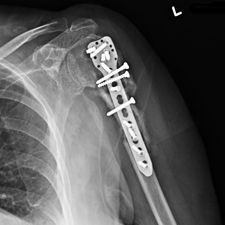

Ms. Q, age 74, initially presented on December 10, 2009, following a multiply comminuted, osteoporotic fracture of her left proximal Humerus. The decision was made to do an ORIF, which was carried out on December 14, 2009. She had a locking plate implanted following which she developed an infection of the wound. She was initially treated with antibiotics for this and she continued to get some oozing of the wound, which did not settle down despite continued use of the various antibiotics including Augmentin. Multiple wound swabs were done which failed to grow any organisms. The oozing persisted until about eight weeks following her operation when it finally settled down and the scar was noted to be tethered and was thought to be tethered onto bone.

She continued to have problems with intermittent cellulitis and pain in the arm and the decision was made to do an early removal of the metal work. This was carried out in mid March 2010 and at operation, which was done through the original incision and anterior extended deltopectoral approach, she was noted to have healed the fracture. She did well postop and was continuing to mobilize.